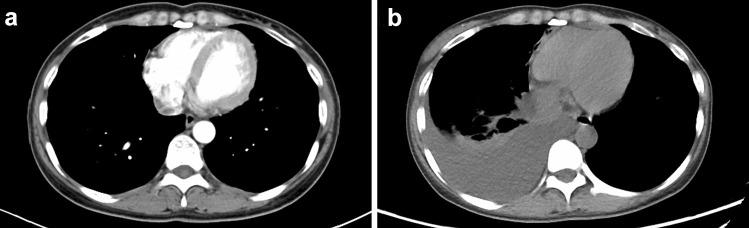

Ceritinib is a new anaplastic lymphoma kinase (ALK) inhibitor that has shown greater potency in patients with advanced ALK-rearranged non-small cell lung cancer, including those who had disease progression in crizotinib treatment. Here we reported, after several months of ceritinib treatment, two patients with advanced ALK-rearranged pulmonary adenocarcinoma exhibited a spectrum of respiratory symptoms like cough and dyspnea, with significantly higher inflammatory indicators. Chest computed tomography (CT) showed multiple bilateral and peripheral lesions in lungs. The prior considerations taken into account were disease progression or infection. However, biopsies of the pulmonary nodules revealed features of granulomatous inflammation without definite cancer cells. We documented for the first time that ceritinib might be associated with pulmonary granulomatous inflammation, and clinicians should be alert to the possibility that the rare adverse event emerged during ceritinib treatment.

塞瑞替尼是一种新型的间变性淋巴瘤激酶(ALK)抑制剂,在晚期ALK 重排的非小细胞肺癌患者中显示出更强的疗效,包括那些在克唑替尼治疗中疾病进展的患者。在这里,我们报告了两名晚期ALK 重排肺腺癌患者在接受塞瑞替尼治疗几个月后出现了一系列呼吸系统症状,如咳嗽和呼吸困难,同时炎症指标显著升高。胸部计算机断层扫描(CT)显示肺部多个双侧和外周病变。先前考虑的因素包括疾病进展或感染。然而,肺部结节的活检显示出肉芽肿性炎症的特征,没有明确的癌细胞。我们首次记录到塞瑞替尼可能与肺肉芽肿性炎症有关,临床医生应该警惕在塞瑞替尼治疗期间出现这种罕见的不良反应的可能性。